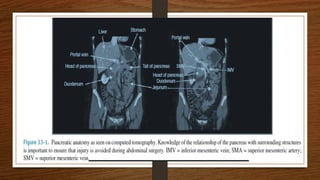

To understand the anatomy and physiology of the pancreas